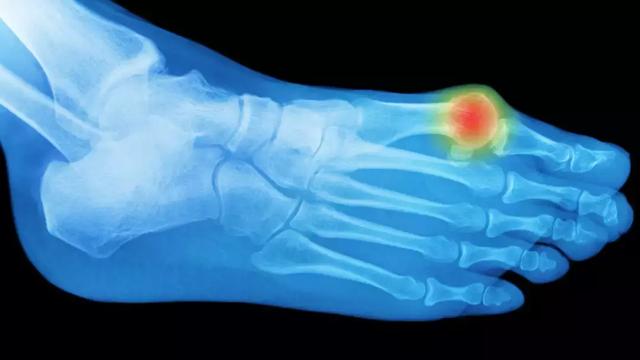

6、足趾痛:痛风

脚痛怎么快速缓解,分享6个简单实用的按摩、伸展动作

可引起关节突然出现灼痛、僵硬和肿胀,常发生在大脚趾关节。痛风的罪魁祸首是尿酸的过量,尿酸是一种自然存在于人体内的物质。虽然你的身体通常擅长调节血液中的尿酸水平,但是过多的尿酸会导致结晶的产生,结晶沉积在关节中。

疼痛通常在夜间发作,并在接下来的八到12小时内强化,之后几天放松。痛风在男性中比女性更常见,不幸的60%的人在一年内会有第二次发作。为了防止今后的攻击,你的医生可能会开处方药物,并建议生活方式的改变,包括改变你的饮食,以降低你的身体的尿酸水平。